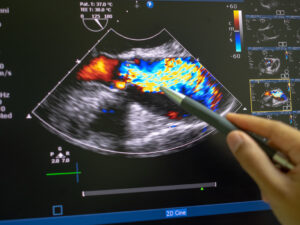

O curso de Ultrassonografia Point-of-Care (POCUS) foi desenvolvido para capacitar profissionais da área da saúde no uso da ultrassonografia como ferramenta rápida e eficaz de apoio à tomada de decisão clínica à beira do leito. Ao longo do curso, o aluno aprende os princípios básicos do ultrassom aplicados ao POCUS, o manuseio prático do equipamento e a execução de protocolos essenciais utilizados em contextos de emergência, terapia intensiva e atendimento ambulatorial. O conteúdo aborda a avaliação de sistemas como cardíaco, pulmonar, abdominal e vascular, com foco na identificação de achados relevantes que auxiliam no diagnóstico imediato e na condução clínica. Com uma abordagem objetiva, prática e direcionada à realidade assistencial, o curso proporciona mais agilidade, segurança e precisão nas decisões clínicas, ampliando a autonomia e a eficiência do profissional no cuidado ao paciente.